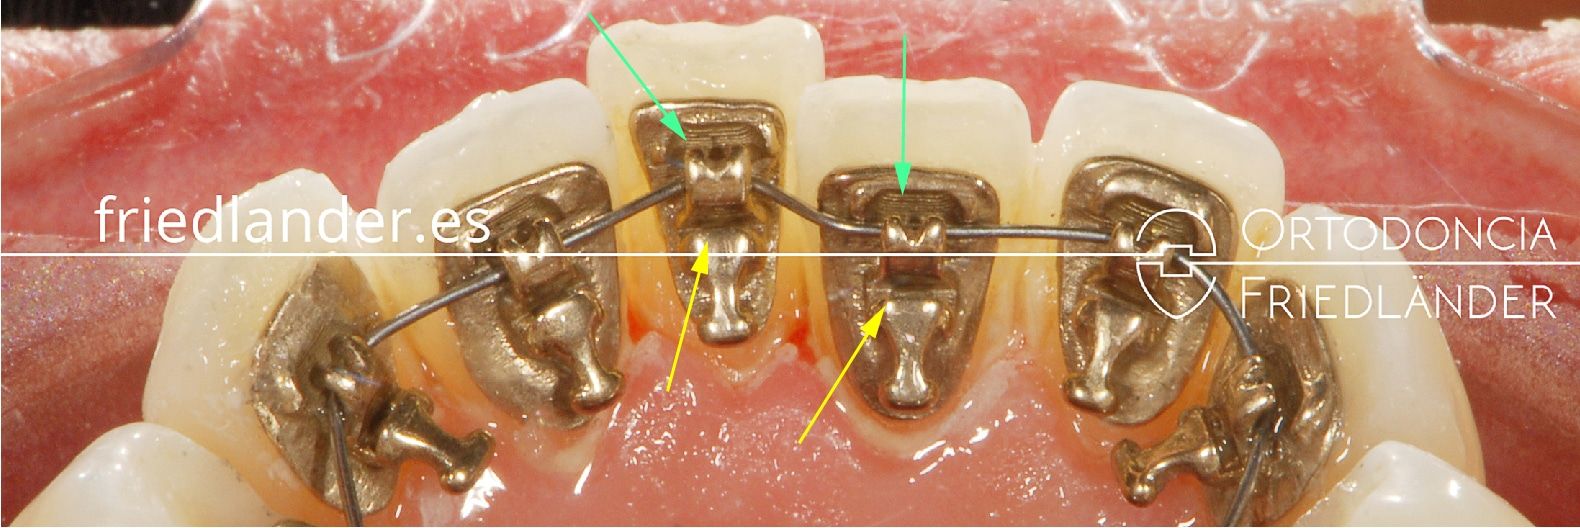

Tratamiento con ortodoncia lingual invisible – Sistema Incognito

Para iniciar la nivelación el alambre fue colocado en la ranura de atuoligado del sistema incognito señalada por las flechas verdes.